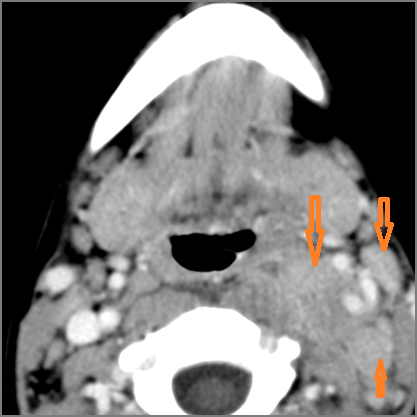

Contrast-enhanced CT of the maxillofacial region and neck and related anatomy with images obtained in the balanced or venous vascular phase to ensure optimal visualization of both arterial and venous structures as well as possible reactive changes around infected collections. 0.5-3.0 mm thick sections were obtained in the axial plane and reformatted 3D and/or in the coronal and sagittal planes and viewed inter actively in 3 dimensions at the computer work station.